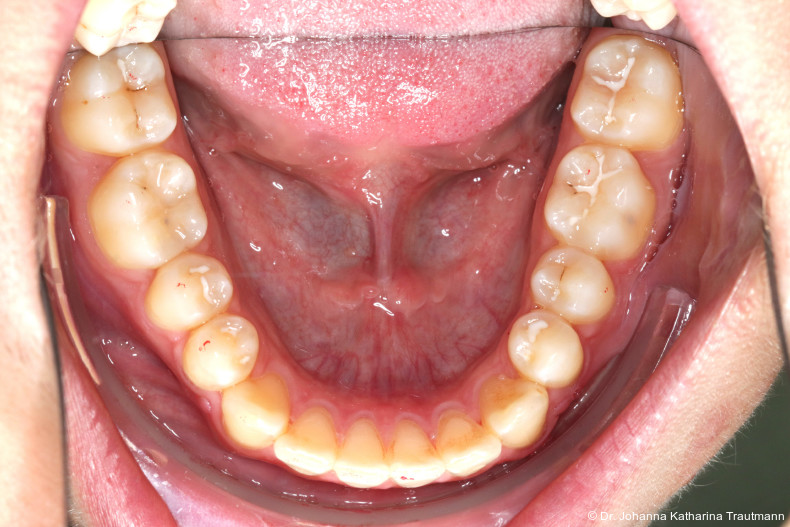

Nach transversaler Nachentwicklung der Maxilla mittels GNE nach Veltri wurde der Zahn 23 geschlossen freigelegt und an einem individualisier ten TPA nach distal angebunden. Zur Aufrichtung der Front und Mesialisierung des hypoplastischen Zahnes 22 kam zusätzlich eine 2x3Mechanik zum Einsatz. Eine rein translatorische Bewegung eines Zahnes ist auch mit einer festsitzenden Apparatur schwer zu erreichen, da der Kraftansatzpunkt nicht identisch mit dem Widerstandszentrum des Zahnes ist.7 Diese Problematik kann einerseits durch das Einbringen eines Versetzungsmomentes adressiert werden, andererseits durch eine Verlagerung des Kraftansatzpunktes. Angelehnt an den von Hong et al. beschriebenen Power Arm 8 wurde hierfür palatinal an Zahn 22 ein cranial gerichteter Hook angebracht (Abb. 3). Da Zahn 22 aufgrund seiner Hypoplasie eine verkürzte Wurzel aufwies, konnte so die Distanz zwischen Widerstandszentrum und Kraftangriffspunkt effizient reduziert werden. Eine weitere biomechanische Schwierigkeit stellte das geringe Alveolarknochenangebot im Spalt bereich mesial von 22 dar. In Bereichen mit Knochendefizit verschiebt sich das Widerstandszentrum nach apikal und wie in diesem Fall zusätzlich nach distal.9, 10 Um dem erhöhten Risiko für Kipp bewegungen entgegenzuwirken, muss hier besonders auf die Steuerung des M/F-Quotienten geachtet werden. Der vestibulär durchgebrochene Zahn 13 benötigte keine Freilegung. Um seine korrekte Einstellung zu ermöglichen, wurde die Mesialwanderung des Zahnes 16 mithilfe des TPAs korrigiert sowie eine Mittellinienkorrektur nach links mittels 2x3 Mechanik durchgeführt.

Nach etwa zwei Jahren initialer Behandlung konnte nach abgeschlossenem Wurzelwachstum aller bleibenden Zähne (mit Ausnahme der Weisheitszähne) mit der Hauptbehandlung unter Verwendung einer vollständigen Multibracketapparatur von 7 bis 7 im Ober und Unterkiefer begonnen werden. Die vergleichsweise lange Vorbehandlung erscheint zwar auf den ersten Blick behandlungszeitverlängernd, sorgt jedoch für eine deutlich bessere Mundhygienefähigkeit sowie für eine Reduktion des apparativen Aufwandes und der biomechanischen Komplexität in der Hauptbehandlungsphase. Diese Faktoren stehen in engem Zusammenhang mit Patientenkomfort und Motivation.

Im Rahmen der Multibrackettherapie wurde bewusst der Zahn 13 aus dem Hauptnivellie rungsbogen ausgelassen, um Kippungen und Asymmetrien im Zahnbogen zu vermeiden. Der Zahn 23 wurde locker mit einer Distanz ligatur angebunden, um eine weitere Bewegung nach vestibulär zu erreichen. Auf einem 0.019" x 0.025" Stahlbogen erfolgte anschlie ßend mittels Umgehungsbiegung sowie eines Overlaybogens (0.014" NiTi) die Integration des Zahnes 13 in den Zahnbogen. Die Zwischendiagnostik nach einem Jahr festsitzender Behandlung zeigte eine gelungene Bisshebung bei guter Nivellierung des Okklusionsplanums und orthoaxialer Einstellung der Frontzähne. Die Zahnbögen präsentierten sich harmonisch ausgeformt, es zeigte sich jedoch eine verbleibende Torqueproblematik an bei den Oberkiefereckzähnen. Nach Freilegung und Einstellung verlagerter Eckzähne ist eine korrekte Torque und Angulationssteuerung häufig eine Herausforderung. Während vestibulär verlagerte Zähne zu gingivalen Rezessionen neigen, behalten palatinal verlagerte Zähne oft ihre palatinale Wurzelstellung bei.13, 14 Die genutzte MBTPrescription der Brackets bietet die Möglichkeit, zwischen +7°, 0° und –7° Torque zu wählen.15 In einem 0.022" System ist bei Verwendung eines 0.019" x 0.025" Bogens jedoch mit einem Torqueverlust von etwa 10° zu rechnen.16